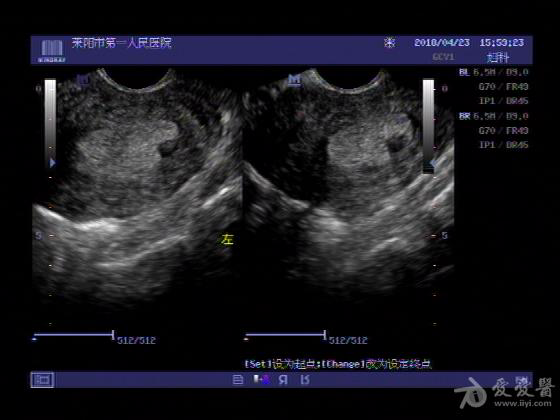

女,48岁,月经量多,两个月,一年前出现过类似现象,刮宫吃药后缓解。

超声可见:子宫内膜显著增厚,后肌壁内膜可见范围约3.27X0.90CM低回声区,CDFI显示较丰富线样血流,宫底宫腔内见类**状低回声结节。前肌壁见多发类圆形低回声结节。

超声提示:子宫内膜增厚(建议刮宫病理),子宫多发肌瘤

病理结果:内膜增生